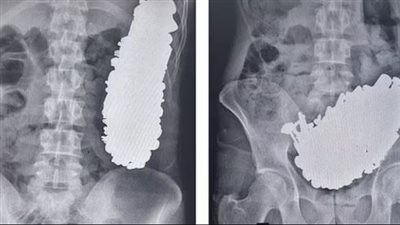

استخراج 3 كيلو مسامير من معدة شاب بإيران